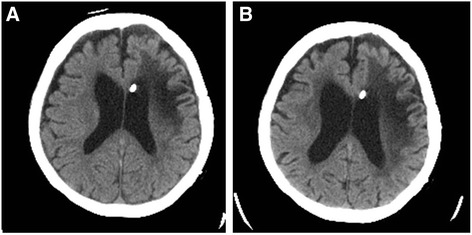

Fig. 3.

Brain CT showed that the ventricle was more dilated and the low-density region around the ventricle had expanded within 7 months (b) after the initial visit to our hospital (a)

The patient was an 84-year-old woman in whom a VP shunt had been placed for normal pressure hydrocephalus after a cerebral hemorrhage at 69 years of age, and she was in a state of dysbasia with an Eastern Cooperative Oncology Group (ECOG) performance status (PS) of 3. While staying in a facility, a mass in the left breast had been noted on a visiting examination by the primary care hospital staff. Since the mass was enlarged, she was examined by a physician. A 3-cm hard mass retracting the dark red skin was palpated on the medial side of the left breast (Fig. 1). Differentiation of a subcutaneous malignant tumor was also considered; however, left breast cancer was suspected according to the ultrasonography findings, and fine needle aspiration cytology (FNAC) was performed. The cytological findings showed increases in the nucleus/cytoplasm (N/C) ratio and chromatin content, an aggregation of atypical cells, and intracytoplasmic lumen. According to these findings, the mass was diagnosed as infiltrating breast cancer. The carcinoembryonic antigen (CEA) level was 8.0 ng/ml, cancer antigen15-3 (CA15-3) was 42.2 U/ml, and breast carcinoma-associated antigen225 (BCA225) was 210 U/ml, all of which were elevated. On whole-body computed tomography (CT), the mass was observed to involve the VP shunt (Fig. 2) and infiltrated the mammary gland over the skin; however, axillary lymph node metastasis and distant metastasis were not observed. Because damage to the shunt due to a needle puncture was a concern, the patient was referred to the neurosurgery department of our hospital; however, there was no problem with the shunt. En bloc resection of the VP shunt and breast was recommended to prevent problems with the shunt, but close observation was selected because her family rejected any treatment. At 7 months after the initial examination, the tumor marker levels were higher: CEA, 9.5 ng/ml; CA15-3, 56 U/ml; and BCA225, 200 U/ml. Skin redness and lethargy developed, and tumor enlargement was observed. A CT scan of the head showed dilated ventricles and the enlargement of periventricular lucency, suggesting that the tumor enlargement caused the obstruction (Fig. 3a, b). Three months later, the patient became bedridden and suffered from aspiration pneumonia due to dysphagia.

Roka et al. reported consciousness disturbance due to hydrocephalus symptoms induced by catheter obstruction by a breast cancer mass [6]. Our case was not treated, and stenosis by catheter compression occurred 7 months after the initial examination. The ventricle was dilated and periventricular lucency expanded, suggesting the aggravation of hydrocephalus. However, the PS and consciousness of our patient was poor from the first visit, thus it was difficult to determine worsening of her condition, except that she was somnolent and bedridden. If the breast cancer was discovered earlier, there might be a possibility that the shunt tube had not been involved with breast cancer. Taken together, partial resection of the breast under local anesthesia may be a treatment of choice leading to convince her family. Therefore, this outcome may have been changed.